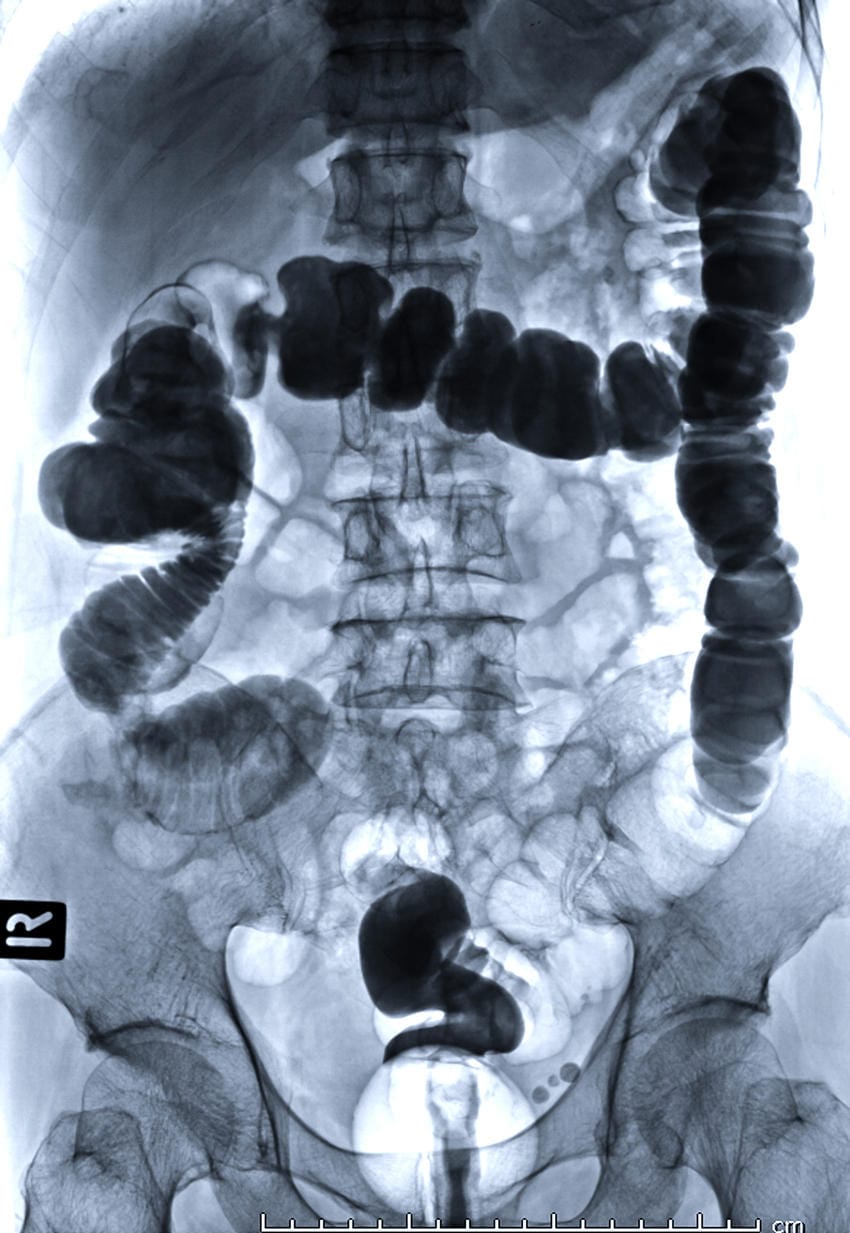

Per clisma opaco si intende una procedura medica strumentale che permette lo studio del colon (anche detto intestino crasso). Nello specifico si tratta di un esame radiologico che utilizza un mezzo di contrasto, ovvero il solfato di bario, grazie al quale è possibile ottenere uno studio dettagliato del lume (interno) del colon e di eventuali sue alterazioni motorie.

- stipsi spastica, con evidente contrattura del colon che divide il mezzo di contrasto in numerose “palle tondeggianti”.

Nella diverticolosi del colon si possono osservare diverse immagini di plus sul profilo del viscere, ad indicare l’ingresso del mezzo di contrasto nei diverticoli. Ad oggi tuttavia la malattia diverticolare va sempre studiata con esame TC e colonscopia, poiché il clisma opaco espone ad un minimo rischio di perforazione diverticolare.

Nei polipi e nei tumori del colon si presentano difetti di riempimento circoscritti ed irregolari che restringono il lume. Spesso la neoplasia diventa stenosante a tal punto da permettere solo il transito di un filo di mezzo contrasto. In questo caso sarà sempre necessario eseguire una TC ed una colonscopia per una maggiore chiarezza diagnostica.